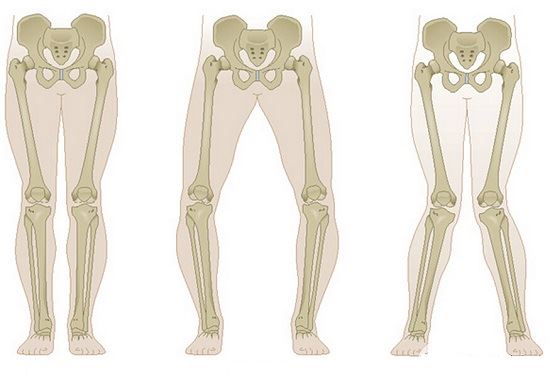

膝关节是一个复杂的机械结构,肌肉长度和力线的改变会引发额外的磨损并导致畸形,关节对缝不正会使局部压力骤增,软组织的紧张和挛缩会让关节软骨加速磨损……这类问题引发的疼痛往往都是酸痛、隐痛,疼痛的位置相对浅表,用手指仔细按压能够找到明确的痛点,疼痛在运动(例如:跑步后)后会有所加重,运动停止后疼痛又很快会减轻。

比较常见的膝关节慢性病变有髌骨软化症、关节软骨损伤、半月板损伤和滑膜炎,多见于中老年人。研究表明,年龄增加、过量运动、缺乏运动、肥胖、关节畸形等因素是膝关节慢性病变的主要诱因,其中又以年龄增加的影响最显著?;痪浠八担ス亟诼圆”涫侨颂謇匣谋厝槐硐?,是一种退行性改变;与此同时,过量运动、缺乏运动、肥胖、关节畸形等因素都可能让膝关节提早出现慢性病变。膝关节慢性病变是骨关节炎的“前奏”,一旦发展为骨关节炎,问题将变得难以挽回。